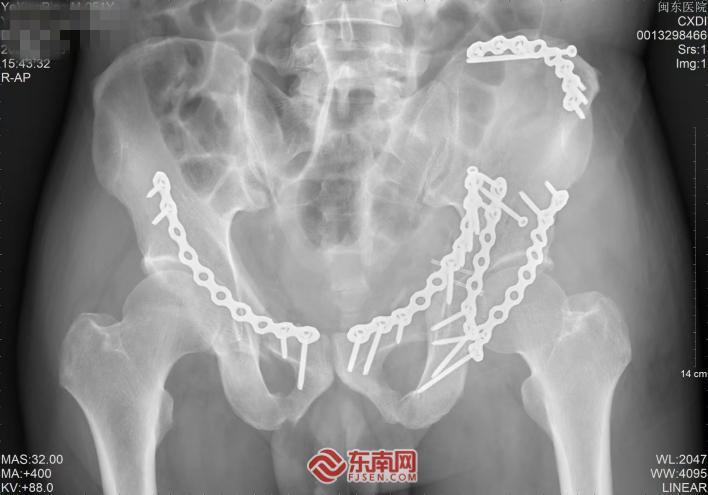

术前影像。闽东医院供图

在郭卫中主任医师带领下,团队利用模型进行了充分的术前“沙盘演练”,确定了最佳手术入路和复位顺序,并预先弯制出与患者骨骼曲面完美贴合的个性化钢板,省去了术中反复弯折钢板的环节,显著缩短了手术时间。

术后影像画面。闽东医院供图

手术过程中,团队沿预定最佳入路精准操作,顺利避开重要血管神经,将预弯定型的钢板完美贴合骨面,实现了“严丝合缝”的解剖复位。术后影像学检查证实,患者髋臼骨折块达到解剖复位,关节面恢复平整,股骨头已稳稳“归位”。